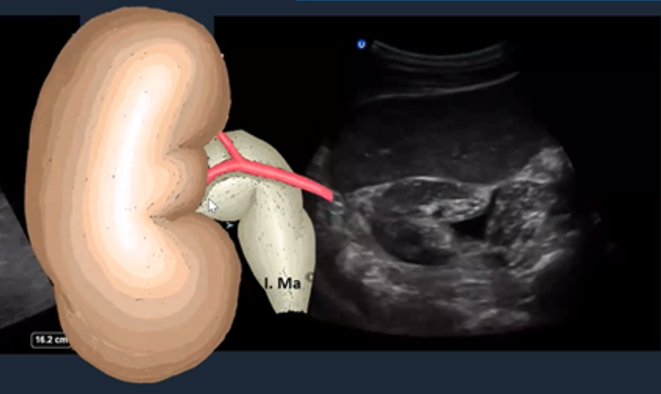

The PSAX view provides a cross-sectional image of the LV, allowing simultaneous visualization of multiple walls. It is the preferred view for global assessment of LVfx and RWMAs. This view is useful for assessing wall motion across the anterior, lateral, posterior, inferior, and septal segments, all seen in a single plane at multiple levels (basal, mid, apical) (figure 11).

A circular LV cavity indicates you’re on-axis, while an oval or elliptical shape suggests you’re off-axis and should adjust your probe angle for a true short-axis view.

Figure 11. PSAX at the mid-papillary level with left ventricular walls labeled.